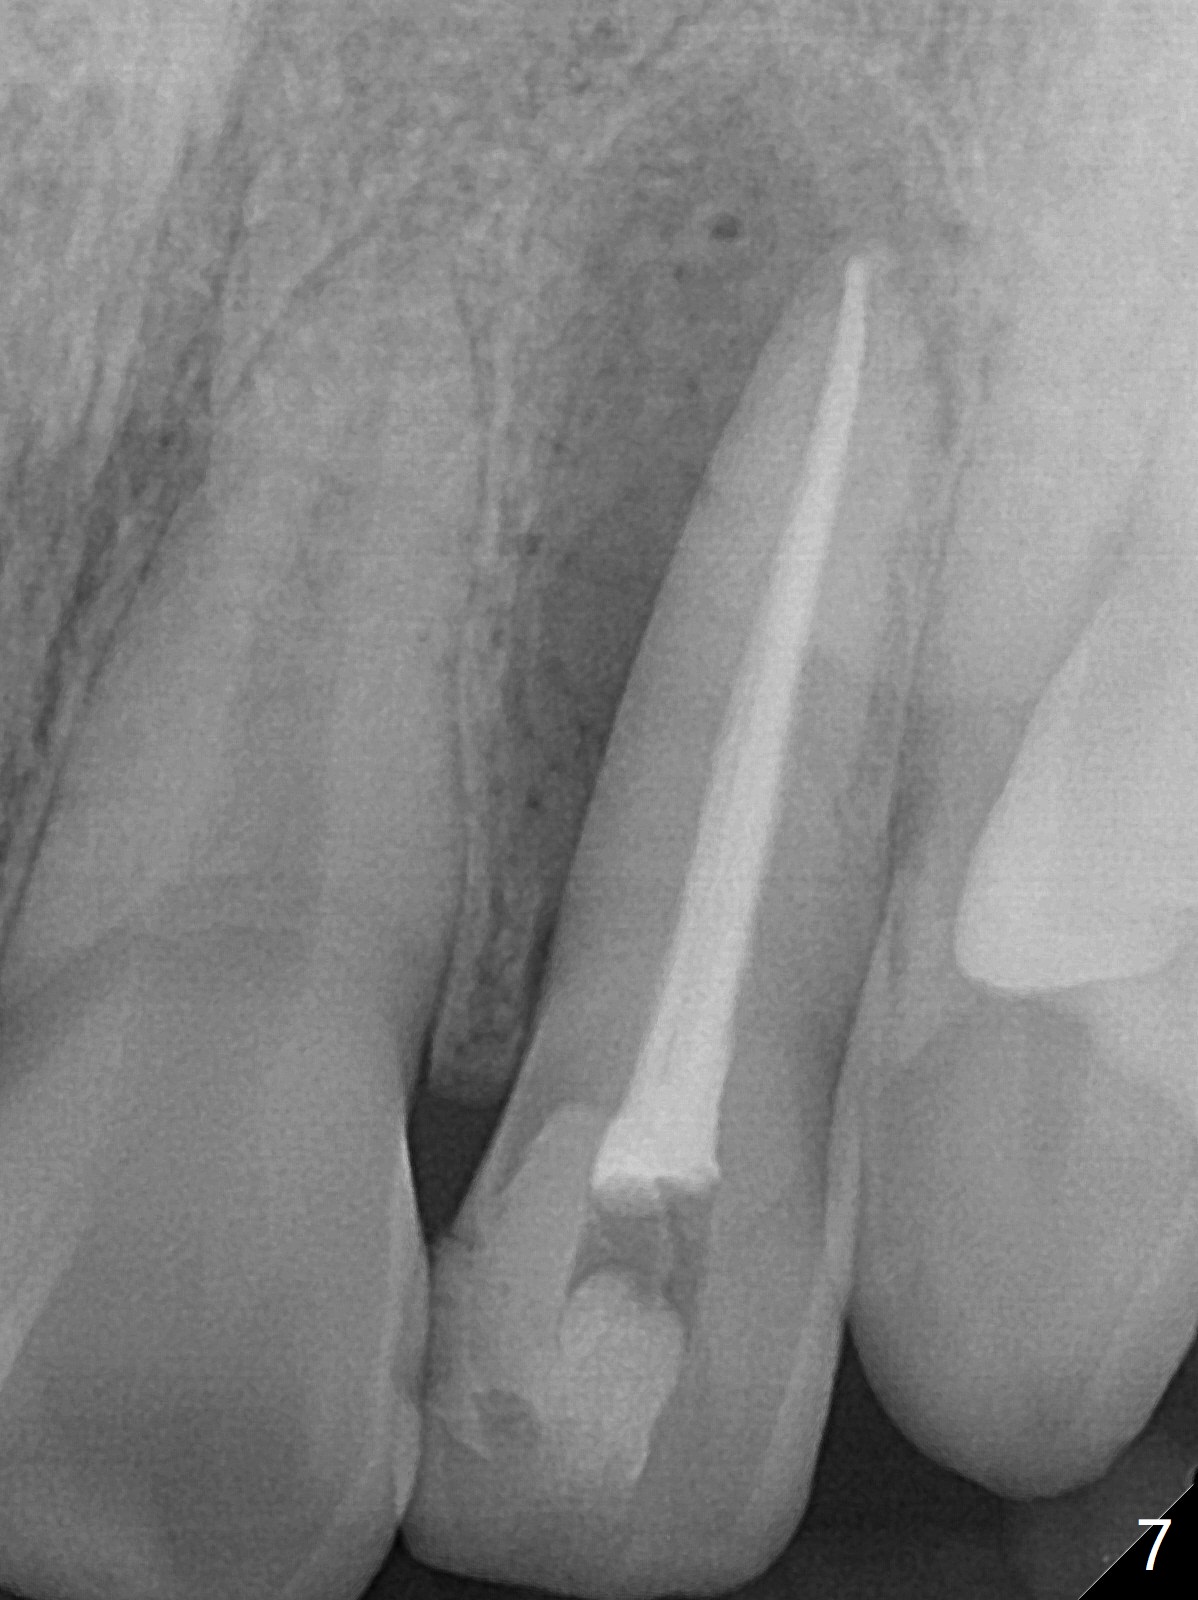

21岁女左上侧切牙根管治疗在别的诊所完成后出现瘘道(图一),近中阴影相当大(图二),应该如何处理?单独重做根管治疗足够吗?牙齿似乎没有松动,牙周袋正常,龋齿易感性高。牙列完整,仿佛没有咬合创伤迹象。可能由于经济问题,家长迟迟不带她去看专家。上个月我开始重做(图三:40/.04),能一次完成治疗吗?保险起见,放置氢氧化钙糊剂(图四)。一个月后病人回来,瘘道减小(图五),多次根管冲洗后,放置主牙胶尖(图六:40/.04),我当时在想根侧方阴影这么大,是不是有侧枝根管?如果扩根完善,根充时可能显示!是吗?其实这是最后根尖片(图七),40/.04主牙胶尖加三个fine, fine accessory gutta percha,并没有显示侧枝根管。